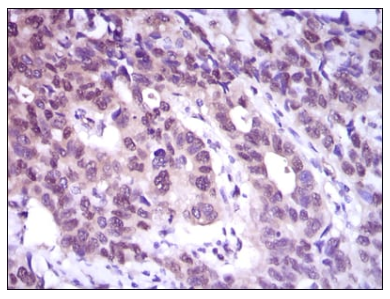

IHC    1/100 - 1/500